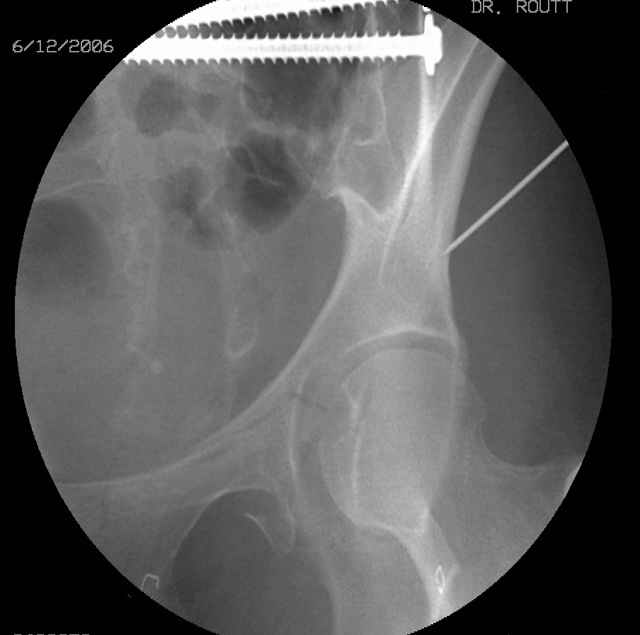

Prone

Here's a pic from the foot of the bed and you can see the clamp in the wound and the knee is extended so he must've had a tight rectus. The C-arm is rolled back to an obturator oblique image to reveal the anterior column...we put a slight outlet tilt to combine the images and give a better view of the anterior column...we can see the posterior column limb reduction in the wound, we can palpate the quadrilateral surface limb, and the image demonstrates the anterior column portion...you can adjust the tilt and rotation to image tangentially to the fracture plane if you'd like. We've inserted a 2mm K wire to site the starting point and aim/orientation for the drill and screw

Prone Imaging

same image, just another look.

OK, now we're inserting the drill percutaneosuy using a sleeve. This fluoro shot is not for this patient (notice no clamp) but I was too lazy to go searching the PACS for one with the clamp on, so pretend...I'll save the next ones and send along...the imaging is the same and the clamp doesn't obstruct imaging other than very rarely...you can always tilt the C-arm a bit to clear it if the clamp obstructs the exact spot that you'd like to see. We'll assume that everyone knows the safe zone for a medullary ramus screw. Use a calibrated drill and sleeve of known length to simplify your life...or use Alex's fancy cannulated screws...I like 3.5mm screws because the oscillating 2.5mm drill bounces and remains intraosseus when it oscillates and contacts endosteal cortical ramus... so will the screw, and like a long bent screw IF the fracture is clamped... if unclamped, when the screw contacts the endosteum, it pushes the reduction apart instead of bouncing. The big 7mm cannulated screws fit few patients and extrude...we very rarely use them any more...you'll see an old one later.

Prone Obturator-Outlet

Screw insertion using the obturator-outlet combination image.